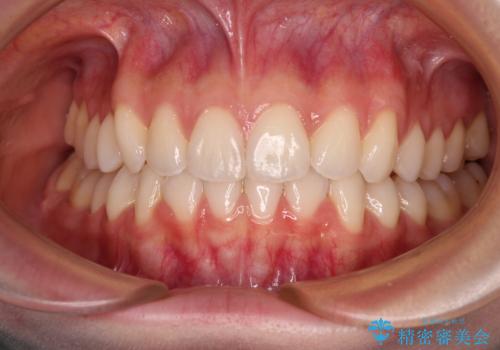

前歯のデコボコと深い咬み合わせ インビザラインできれいに改善

インビザラインによる上下歯列の拡大と、IPR(歯と歯の間を削る)にるスペースの獲得により、口元のデコボコとディープバイトを改善することとしました。

インビザラインは、装着していない時間がどれだけ短いかが、治療期間を大きく左右します。こちらの患者様は1日22時間以上、毎日欠かさず装着してくださったため、1年弱という短期間で満足のいく歯列に整えることができました。